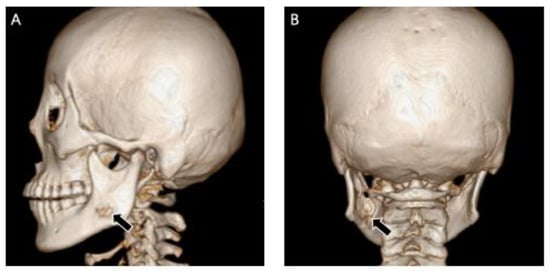

2.2. Case 2